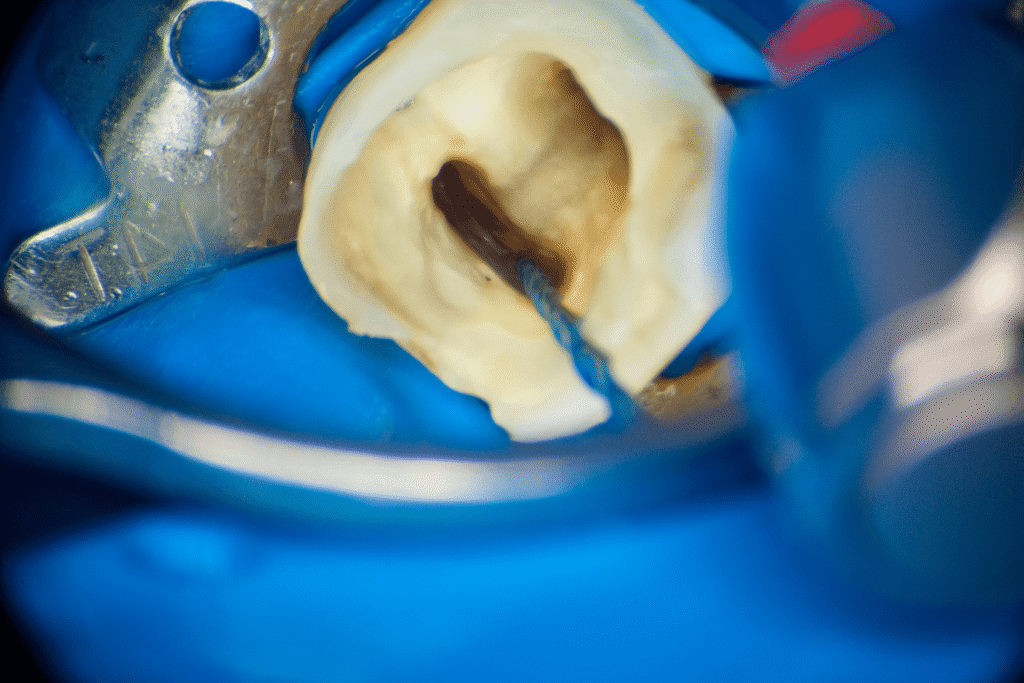

Pacjentka lat 54 trafiła do mojej kliniki skierowana z innego gabinetu celem leczenia endodontycznego zęba 46. W badaniu stwierdziłem znaczny zanik światła kanału korzeniowego. W badaniu tomograficznym stwierdziłem całkowity zanik kanału korzeniowego w strefie mezjalnej. Korzeń dystalny mimo widocznego światła kanału na CBCT, widoczne było wiele zwapnień w środkowej części kanału. Po wykonaniu dostępu endodontycznego zlokalizowałem materiał wypełniający kanał pozostawiony po poprzednim nieskutecznym leczeniu endodontycznym. Do usunięcia wykorzystałem laser 2780nm (25mJ/puls). W kolejnych etapach instrumentacji wspomaganie ultradźwiękami oczyściłem strefy mezjalną i dystalną. Instrumentacja themo-

mechaniczna polegała na zastosowaniu protokołu ciągłej chelacji wraz z użyciem lasera

2780nm z końcówką płaską (50mJ/puls) celem udrożnienia przestrzeni endodontycznych. Po wstępnym uzyskaniu drożności zastosowałem instrumentację maszynową wspomagająco celem udrożnienia przestrzeni. Finalnie obturacja z zastosowaniem ćwieków gutaperkowych kalibrowanych na WL i uszczelniacza na bazie krzemianów wapnia. W przeciwieństwie do tradycyjnych uszczelniaczy, nie wymaga mieszania, co eliminuje błędy w proporcjach i zapewnia powtarzalną konsystencję. Jest materiałem wysoce biokompatybilnym i bioaktywnym. Finalnie zamknięto ząb odbudową kompozytową tymczasową i skierowano na dalsze leczenie protetyczne do gabinetu kierującego pacjenta.